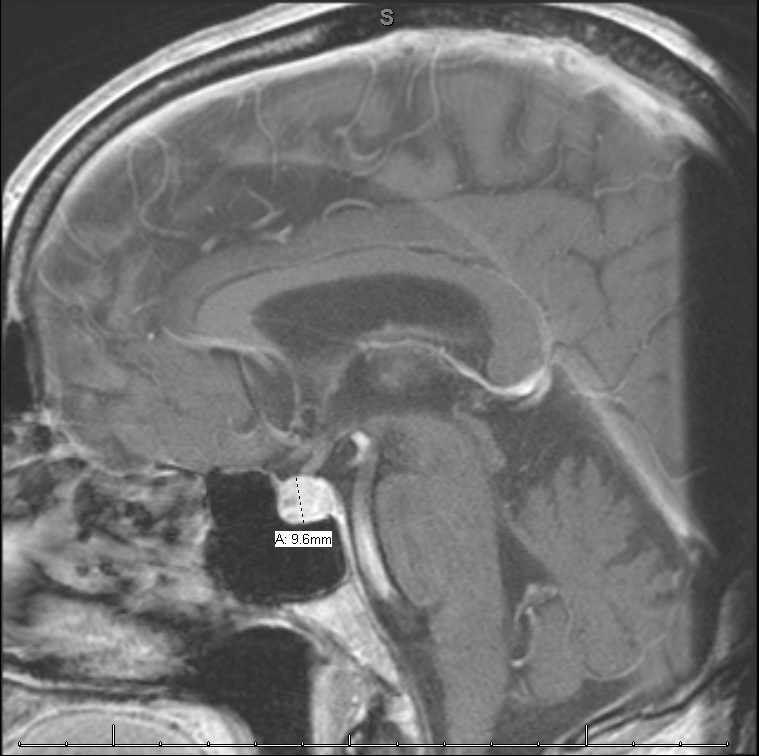

The patient was brought to the emergency department where his vital signs were notable for a fever to 100.8 and hypotension to 85/47 mmHg. He was given vancomycin, cefepime, and 2.5L NS for suspected sepsis. Laboratory analysis was notable for a white blood cell count of 10.8 thousand with a normal differential, Na 128 (mmol/L), Thyroid stimulating hormone 0.018 (mIU/L), T4 0.3 (ng/dL), cortisol 0.8 (mcg/dL), luteinizing hormone (0.3mIU/mL), adrenocorticotropic hormone (below lower limit), and urinalysis with 16 white blood cells and positive leukocyte esterase. He was started on IV hydrocortisone with a 100mg immediately followed by 50mg every 8 hours for a total of 6 doses. His hyponatremia and hypotension resolved rapidly. A brain MRI showed an enlarged and enhancing pituitary gland. CT of the abdomen and pelvis showed bilateral adrenal masses (decreased in size from priors) without adrenal hemorrhage as well as an 8mm ureteral stone. He underwent urgent cystoscopy and stone removal with stent placement. Post operatively he was started on 50mcg of levothyroxine. He was transitioned to oral hydrocortisone 50mg every 12 hours for 1 day, then 25mg every 12 hours, which is the dose that he was discharged on. He completed a total of 7 days of antibiotics 4 days of cefepime while hospitalized and 3 days of cefpodoxime.